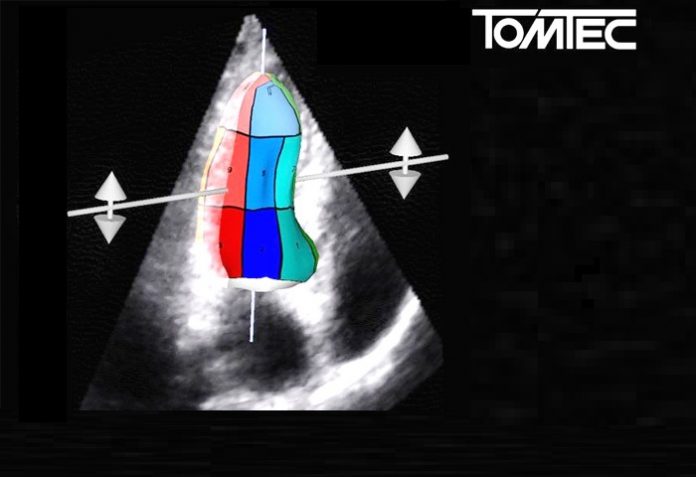

Display of 2D Strain Analysis with 2D Cardiac Performance Analysis©, TomTec

Cardiac imaging is needed to display and assess both morphology and function of the beating heart. Cardiac Ultrasound offers the best enabling technology for a combined analysis of the morphological as well as the functional aspects. Using new algorithms based on a speckle-tracking technique (2D Cardiac Performance Analysis©, TomTec), may result in a more precise quantification of myocardial function. In addition there is a possibility to quantify wall motion abnormalities and dyssynchrony, which may lead to a more precise clinical decision.